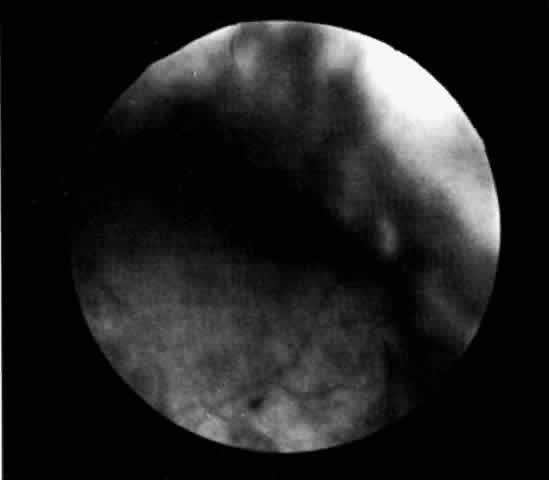

The presence of certain clinical characteristics may assist in the diagnosis of a ciliochoroidal effusion (Table 1). One clinical feature is choroidal edema. Choroidal edema may resemble a retinal detachment to a hasty observer; however, darkness of the uvea, lack of tremulousness, and normal retinal vessels indicate a probable uveal process (Fig. 1). The effusion may extend under the pars plana, allowing visualization of the ora serrata without scleral depression (Fig. 2).9 As shown in Figure 2, the surface of the elevation is convex and smooth, with a solid appearance and a homogeneous grayish color. A shallow anterior chamber and a low intraocular pressure may also suggest the diagnosis. Myopia in the presence of anterior displacement of the lens-iris diaphragm may be another diagnostic clue.10,11

Fig. 1. Painting of the ophthalmoscopic features of uveal effusion syndrome. There is a diffuse pigmentary disturbance in a dot, blot, or linear configuration and an annular ciliochoroidal effusion with secondary inferior retinal detachment.